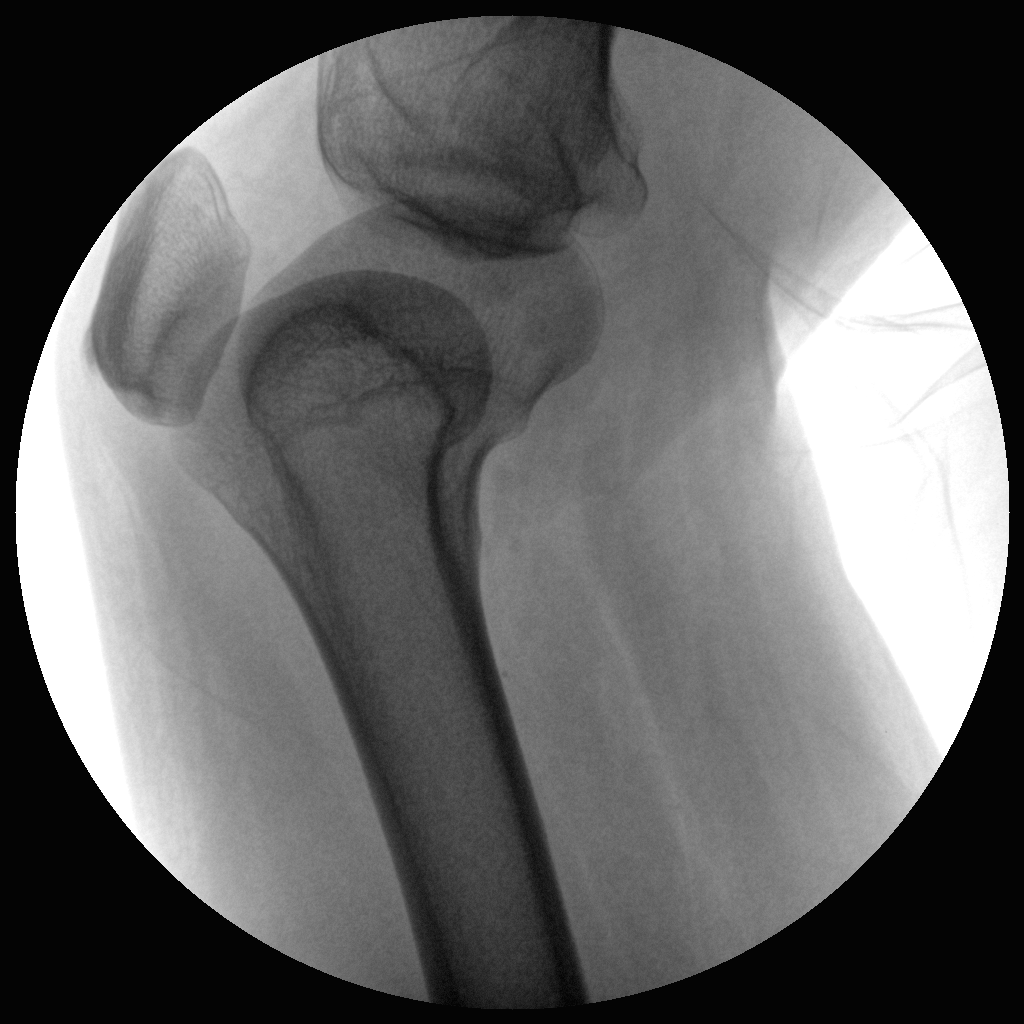

Clinical picture

臨床圖片